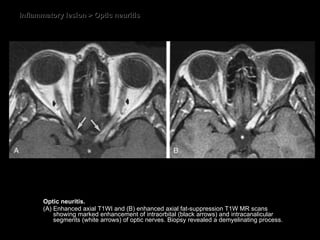

Optic neuritis CT some enlargement of the optic nerve some degree of contrast enhancement.  MRI Thickened and hyperintense T2WI. Diffuse enhancement within the nerve on T1WI FS. Evidence of MS plaques

Inflammatory lesion > Optic neuritis Optic neuritis.  (A) Enhanced axial T1WI and (B) enhanced axial fat-suppression T1W MR scans showing marked enhancement of intraorbital (black arrows) and intracanalicular segments (white arrows) of optic nerves. Biopsy revealed a demyelinating process.